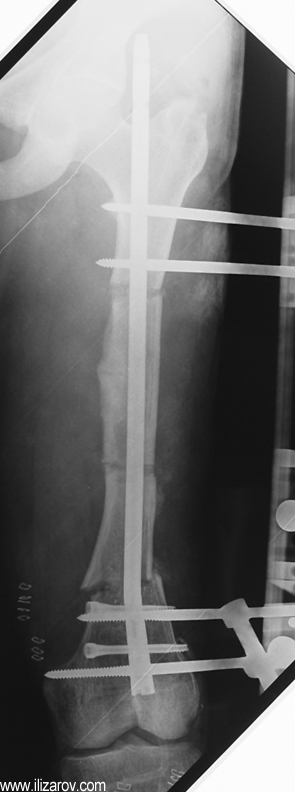

Because the deformity caused by hypophosphatemic rickets is very close to the growth plate, a significant deformity and malalignment occurs. For that reason, more than one deformity centers (CORA) are found at preoperative evaluation, and osteotomy at more than one level is required to correct the deformity. The most frequently used methods to correct the deformity are acute or gradual deformity correction using the Ilizarov method or unilateral external fixator. In the ‘fixator assisted nailing’ technique, which is applied in our department, the deformity is corrected in an acute fashion with the help of an external fixator, and the extremity is stabilized by an intramedullaru nail. The external fixator is removed before the end of the surgery if no gradual lengthening is planned postoperatively. If lengthening (over nail) is planned, the fixator is removed after the completion of the lengthening procedure. As a result, the risk of pin tract infection is eliminated, correction loss and relapsing of the deformity (which are important problems in the treatment of hypophosphatemic rickets) are avoided, eary motion and full weight bearing are allowed, and comfortability of the patient is improved because the duration with external fixator is decreased.

Case 2